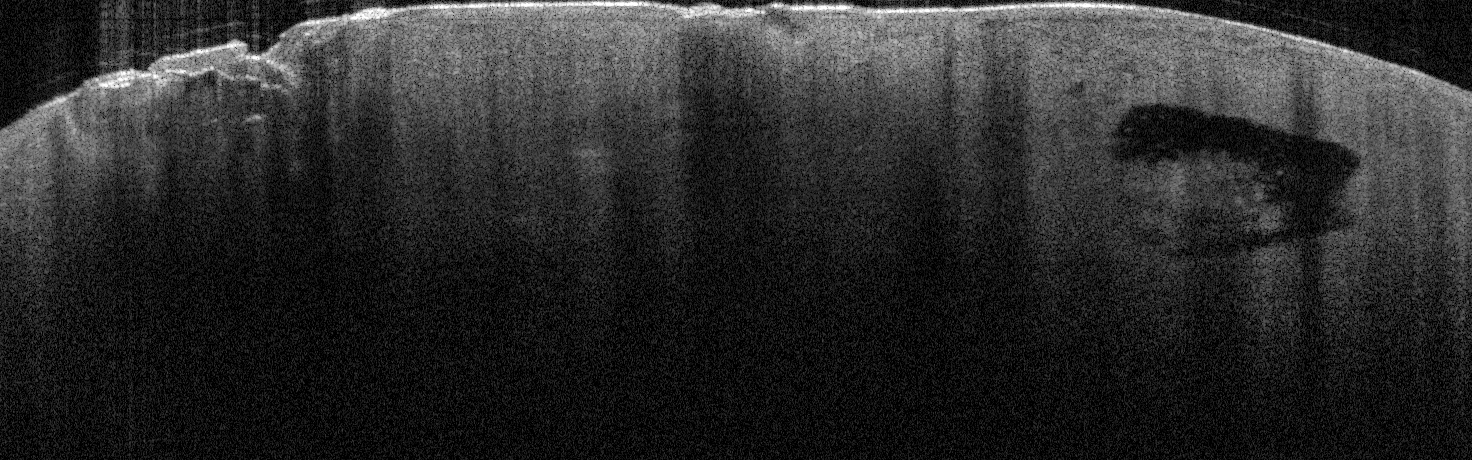

VA54: Left Superior Temple, Adjacent, Normal